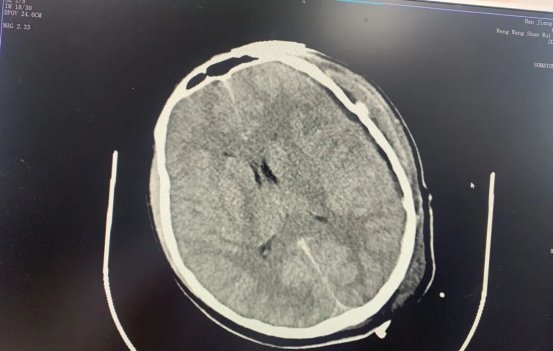

影像结果很快传来:颅骨骨折脑肿胀明显,硬脑膜下血肿迹象明显,若不及时手术,颅内压持续升高将压迫脑组织,随时引发脑疝危及生命。“必须马上手术!”神经外科吴明生副主任医师第一时间判断病情,同时一面安抚焦急的家属、清晰告知手术必要性,一面迅速协调手术室、麻醉科做好准备,为后续救治抢出关键时间。

颅脑外伤手术容错率极低,尤其小羽年纪尚轻,手术方案需兼顾“精准清除病灶”与“保护脑组织功能”。神经外科吴明生副主任医师、余俊杰副主任医师组成“攻坚小组”,为小羽制定了“左侧开颅血肿清除”的手术方案。

迅速完成术前准备后,手术正式开始。按照预设方案,医护人员在小羽头顶小心翼翼打开一个14cm×12cm的骨窗,这一尺寸既足够暴露血肿区域,又避免过度扩大创伤。术中探查发现,硬脑膜下血肿量约40ml,如同一颗“定时炸弹”压迫脑组织,需要立即清除,清除后继续探查发现,上矢状窦引流静脉存在破裂,血液正持续渗出。“稳住,先控制出血!”吴明生副主任医师迅速止血。最后医护人员精准固定颅骨、分层缝合头皮,整个手术历时2小时40分钟,全程零失误,顺利完成。